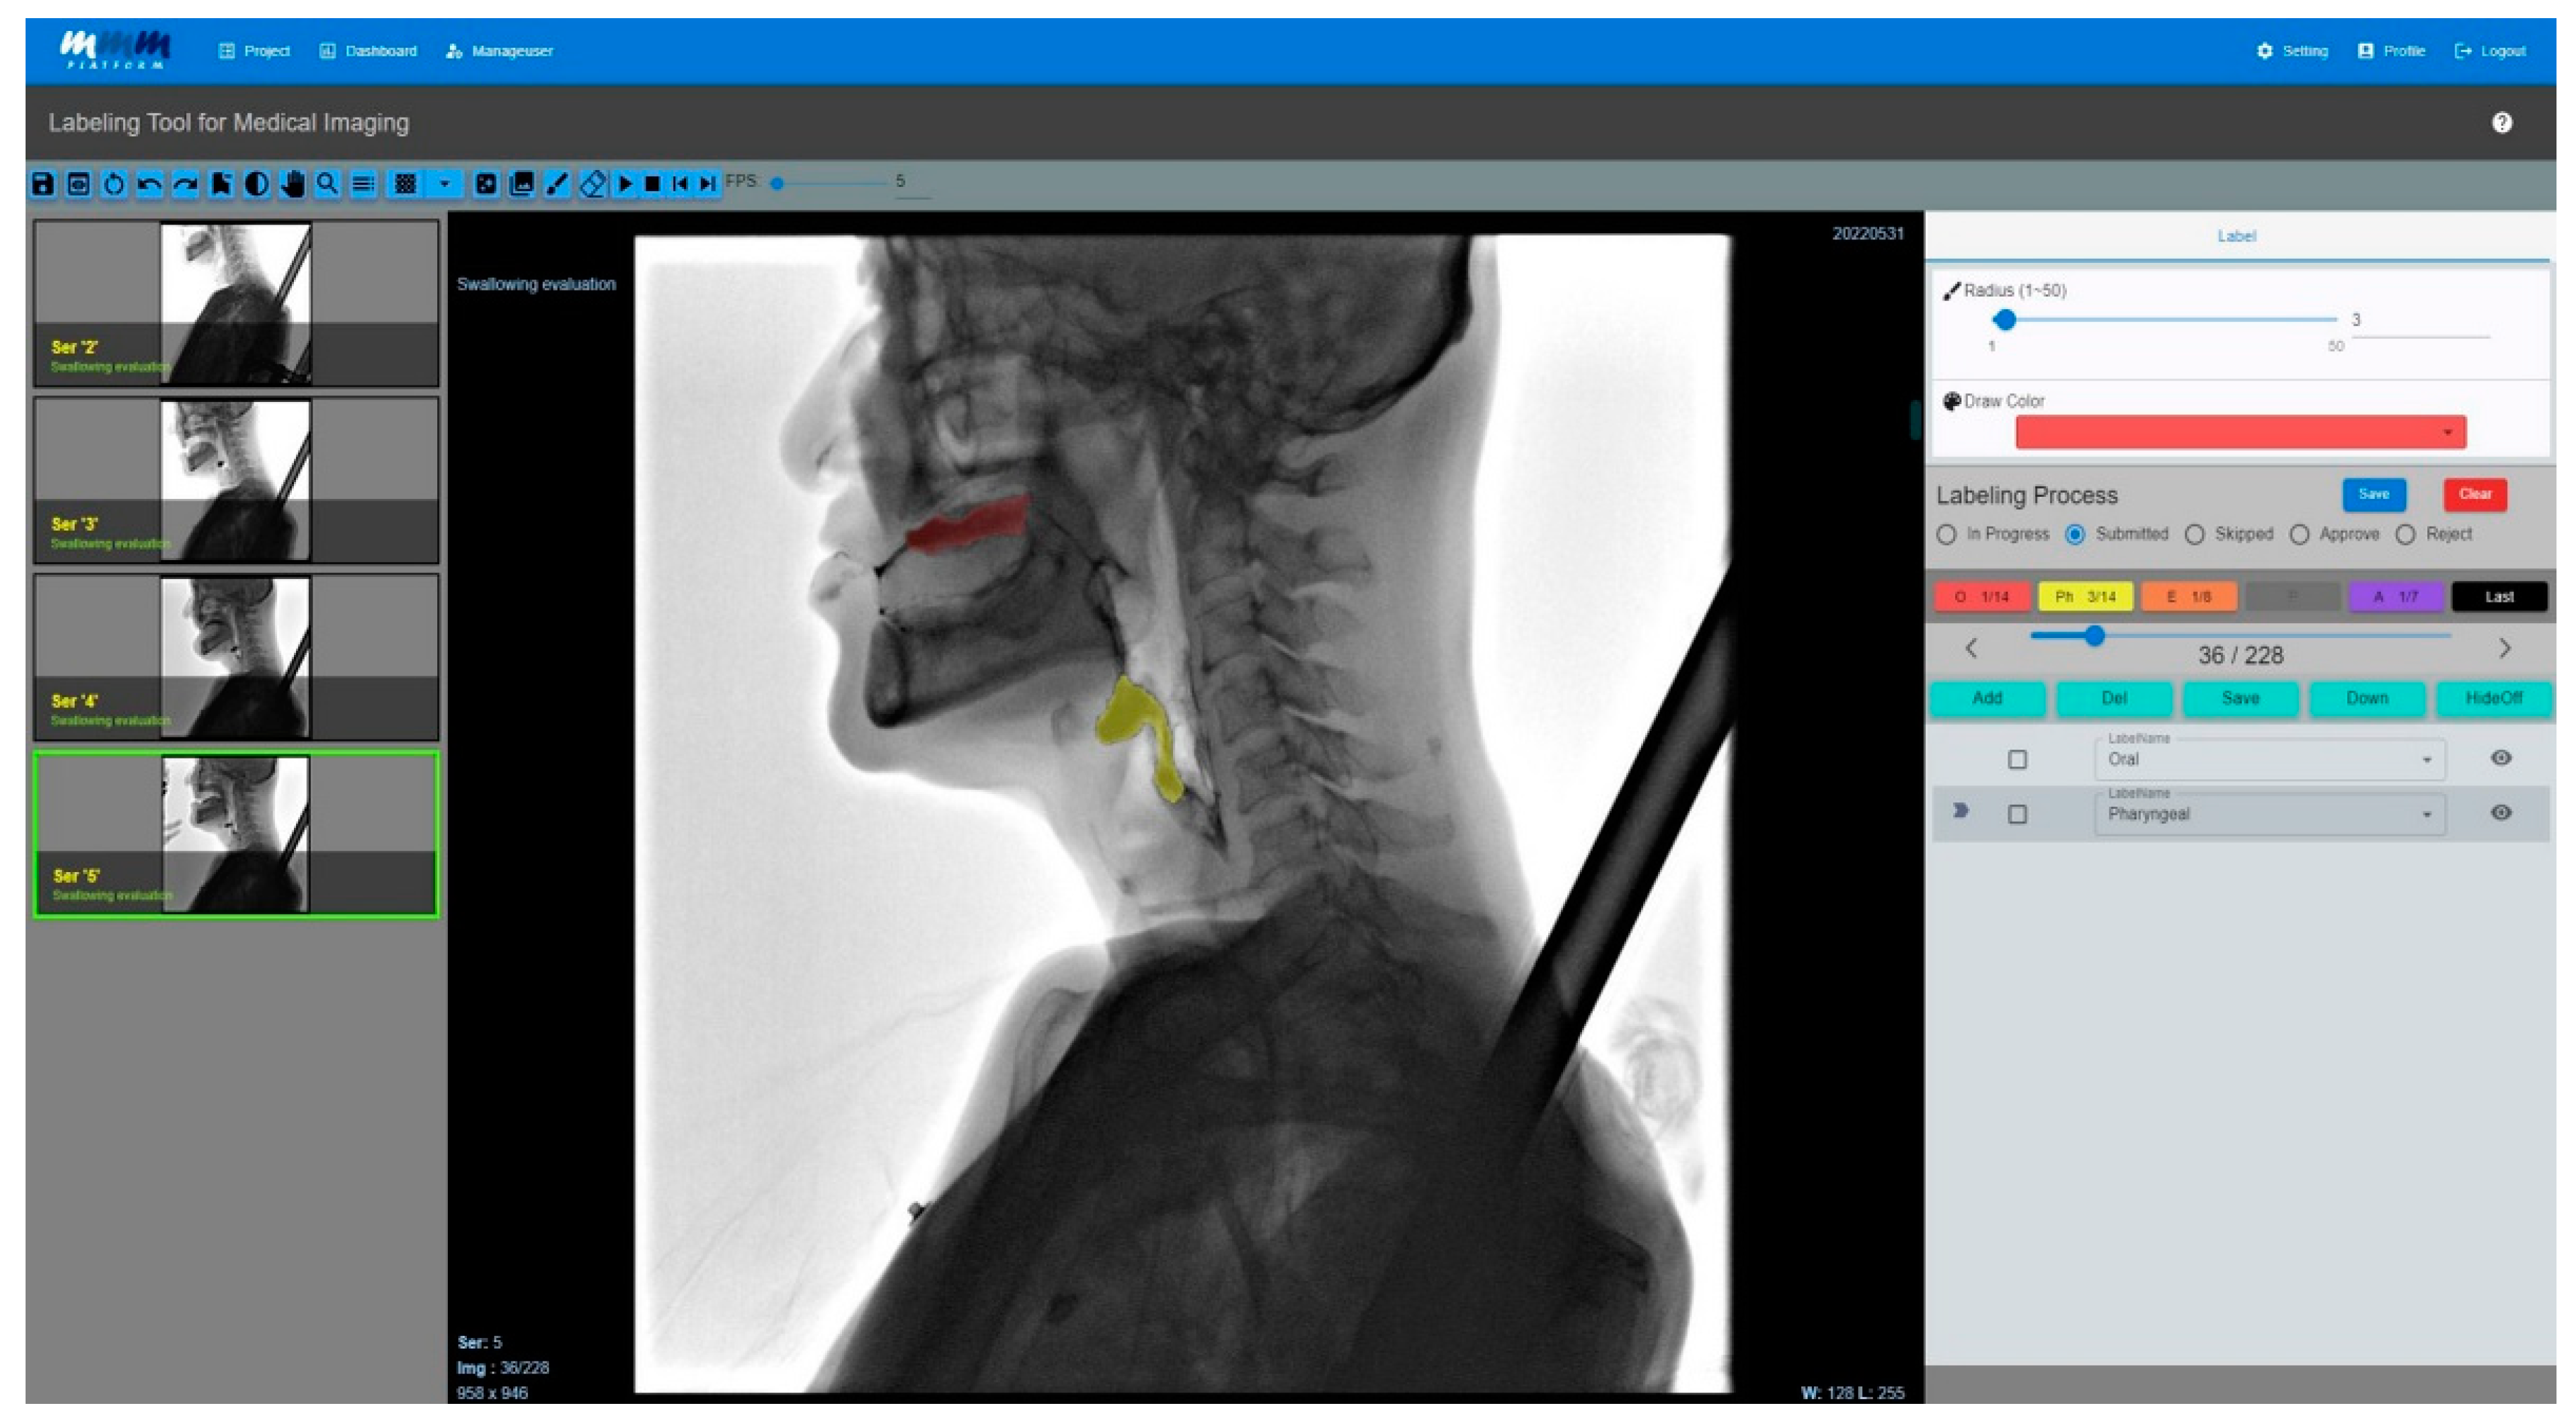

The complete user interface of the medical image-labeling web application is shown in Figure 4; its operation involves checking through the viewer in the labeling tool.

Figure 5 shows the results of labeling the food material as it moves from the pharyngeal phase to the esophageal phase and from penetration to aspiration by loading the entire image divided by frames to mark the multiframe image. In particular, a function for labelers was added to perform the labeling, and an approval process was added for the final clinician to approve the labeled data.

Figure 4. The user interface of the medical labeling web application. In order to label the multiframe image, the entire image was uploaded and divided by frame. The video was labeled as the food material progressed from the oropharyngeal to the esophageal phases. It also showed the results of the labeling images that track the food bolus as it invades the airways. In particular, there is a process for the labeling results performed by the technician to be approved by doctors specializing in swallowing disorders, designed to increase the precision of the labeling.